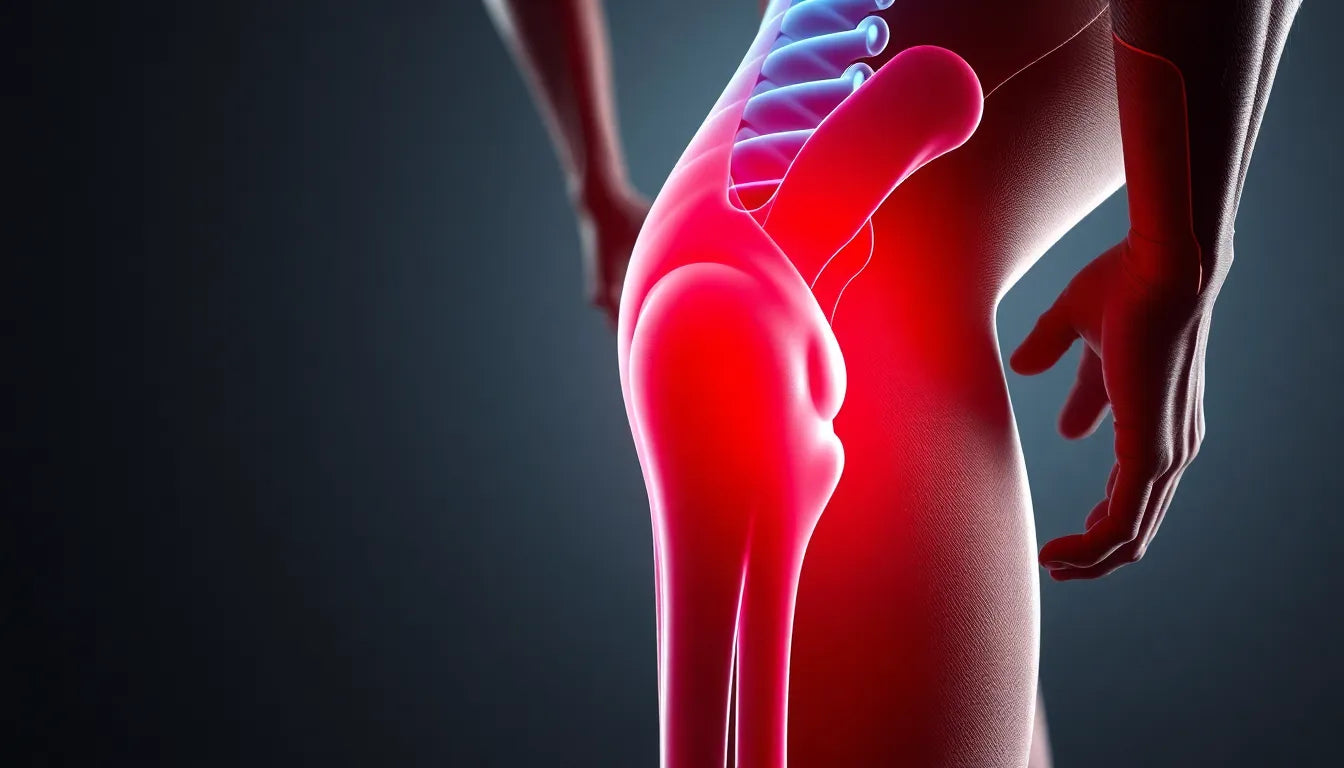

Smerter in de onderrug en misselijkheid zijn symptomen die vaak samen voorkomen, en voor veel mensen kunnen ze een bron van zorg zijn. Of je nu last hebt van een zeurende pijn in je onderrug of plotselinge aanvallen van misselijkheid, het is belangrijk om te begrijpen wat deze symptomen kunnen betekenen. Vaak kunnen ze wijzen op relatief onschuldige problemen, maar soms kunnen ze ook een teken zijn van ernstigere gezondheidsproblemen.

Smerter in de onderrug en misselijkheid zijn symptomen die vaak samen voorkomen, en voor veel mensen kunnen ze een bron van zorg zijn. Of je nu last hebt van een zeurende pijn in je onderrug of plotselinge aanvallen van misselijkheid, het is belangrijk om te begrijpen wat deze symptomen kunnen betekenen. Vaak kunnen ze wijzen op relatief onschuldige problemen, maar soms kunnen ze ook een teken zijn van ernstigere gezondheidsproblemen.

Het begrijpen van de oorzaken van pijn in de onderrug en misselijkheid is cruciaal om de juiste beslissingen te nemen over het zoeken naar medische hulp of het toepassen van zelfzorgstrategieën. Deze symptomen kunnen immers variëren van tijdelijke ongemakken tot signalen van onderliggende aandoeningen die medische aandacht vereisen. Door te weten wat de mogelijke oorzaken zijn, kun je beter inschatten wanneer het tijd is om professionele hulp in te schakelen.

In deze blogpost verkennen we de mogelijke oorzaken van deze symptomen, bieden we praktische adviezen en geven we een gids voor wanneer medische hulp noodzakelijk is. Je leert meer over hoe aandoeningen zoals maag-/darminfecties, galstenen, en coeliakie kunnen bijdragen aan deze symptomen. Ook bespreken we de ernstigere oorzaken en de rode vlaggen waar je op moet letten. Tot slot bieden we praktische tips voor zelfzorg, zoals het belang van beweging en het gebruik van ergonomische hulpmiddelen.

Mogelijke oorzaken van lage rugpijn en misselijkheid

Wanneer je te maken hebt met een combinatie van lage rugpijn en misselijkheid, kan dit diverse oorzaken hebben. Een veelvoorkomende reden is een maag- of darminfectie. Deze infecties kunnen leiden tot ontstekingen die niet alleen misselijkheid veroorzaken, maar ook druk uitoefenen op omliggende structuren, wat resulteert in rugpijn. Een andere veelvoorkomende oorzaak is gastro-oesofageale refluxziekte (GERD), waarbij maagzuur terugvloeit in de slokdarm en zowel misselijkheid als rugpijn kan veroorzaken.

Galstenen en pancreatitis zijn eveneens aandoeningen die vaak gepaard gaan met deze symptomen. Galstenen kunnen de galwegen blokkeren en een scherpe, uitstralende pijn naar de rug veroorzaken. Pancreatitis, een ontsteking van de alvleesklier, kan ook leiden tot ernstige buikpijn die naar de rug uitstraalt, vaak samen met misselijkheid.

Coeliakie, een auto-immuunziekte die wordt veroorzaakt door glutenintolerantie, kan ook bijdragen aan deze symptomen. Mensen met coeliakie kunnen last krijgen van buikklachten en rugpijn als gevolg van de ontstekingsreacties in hun darmen, die ook misselijkheid kunnen veroorzaken door malabsorptie van voedingsstoffen.